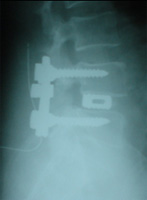

DISC SURGERY LYSTHESIS CORRECTION

SPINAL TRAUMA & DEFORMITY CORRECTION